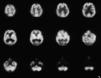

Fig. 1. Ejemplo de SPECT no alterado.

Fig. 2. Ejemplo de SPECT alterado. Se comprueba en la imagen la hipocaptación occipital bilateral.